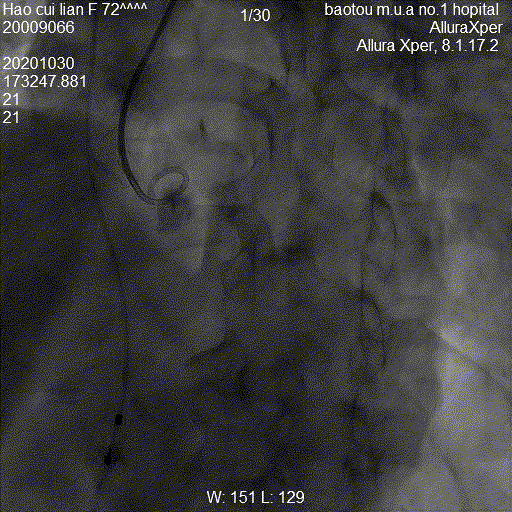

图:手术流程图